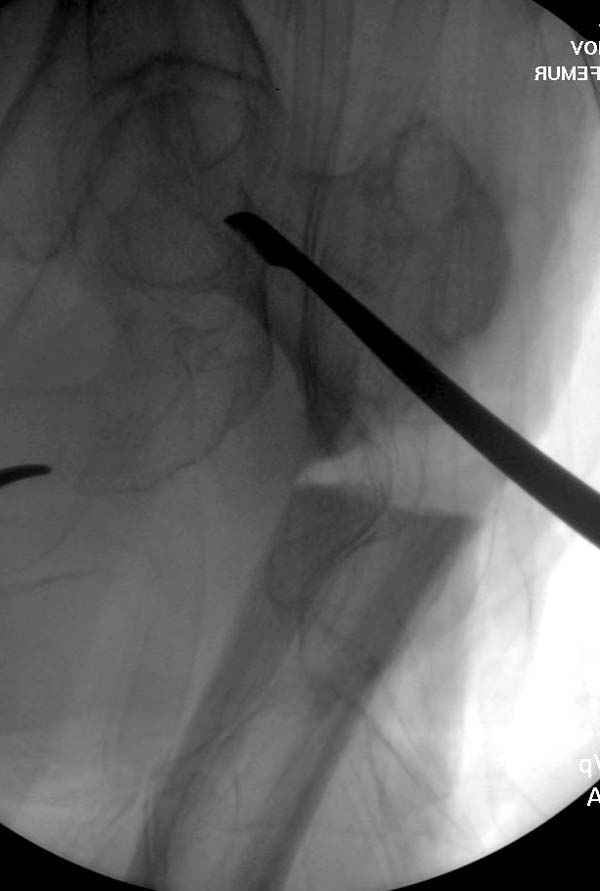

77 летняя больная направлена в нашу клинику на дальнейшее лечение. Из истории, травму получила в сентябре 2007 года и по поводу перелома шейки бедра больная была проперирована тремя каннюлированными шурупами с явным нарушением технологии установки шурупов. Внизу вместо одного шурупа имеется два, что привело к стрессу латерального кортекса. Через месяц по поводу ятрогенного подвертельного перелома сделана фиксация длинной Гамма 3. Установлен без проксимальной блокировки? (set screw). В данный момент имеется несостоятельность конструкции и ложный сустав. Передвигается с помошью костылей, конечность укорочена на 2 см. Какие будут рекомендации?Djoldas Kuldjanov, MDDepartment of Orthopedic SurgerySt. Louis University Medical Center

Видимо, проблем тут две: во-1-х, центральный отломок был оставлен в варусно-сгибательной установке, во-2-х, не динамизировали вовремя.

Нижние винты хотели сломаться, но, увы, один не сломался, и тогда сломался гвоздь. Хотя и при динамизации в таком положении отломков

могло не срастись.

Не стали усложнять интрамедуллярным вариантом коррекции, легче контролировать коррекцию пластиной, поэтому сделали операцию 95 градусной Blade Plate, разогнув до 110 градусов.

Надеемся на успех, потому что до введения пластины дефект от импланта забили костной стружкой и удалось создать компрессию между отломками, максимальную для импланта (150 кило/паунд). Сделана дополнительная костная пластика и за счет измененного угла пластины устранено укорочение конечности.

Страйкер предоставил отличный инструмент - крючок для удаления длинного гвоздя. Считаем, что врачебная ошибка по установке привела к несостоятельности импланта и к ятрогенному осложнению.